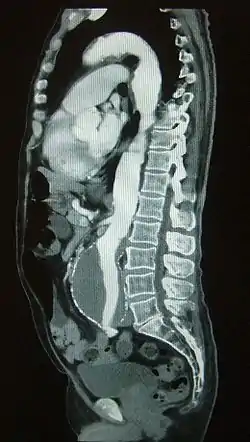

![]() Seguimiento de un bolo de contraste en su paso por la arteria aorta evidenciándose un aneurisma aórtico | ||

En la angiografía por TAC, el análisis se realiza simultáneamente con una inyección de medios de contraste a alta velocidad hasta que alcance el lecho arterial de interés, empleando una técnica que le hace seguimiento a la trayectoria del bolo inyectado.[1] En comparación con la angiografía por catéter, que consiste en colocar un catéter de calibre importante e inyectando a través de éste el material de contraste dentro de una gran arteria o vena, la angiografía por TAC es mucho menos invasiva y menos incómoda para el paciente. El material de contraste se inyecta en una vena periférica mediante el uso de una pequeña aguja o cánula intravenosa. Este tipo de examen se ha utilizado para examinar a un gran número de personas en busca de enfermedades arteriales.